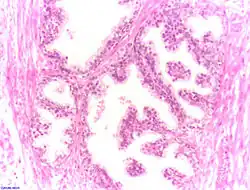

97 % aller Prostatatumoren sind Adenokarzinome, das heißt, sie entstehen aus entarteten Drüsenzellen. Ein Übergangsstadium zum manifesten Krebs wird als prostatische intraepitheliale Neoplasie (PIN) bezeichnet und entspricht einem Carcinoma in situ. Beim eigentlichen Karzinom kommen verschiedene histopathologische Wachstumsmuster vor, auch gleichzeitig nebeneinander: glandulär beziehungsweise azinär (drüsenartig), kribriform (siebartig) und solide. Das Ausmaß der Entdifferenzierung ist Grundlage des Gradings. 40–50 % der Tumoren liegen bei Diagnosestellung multifokal vor.[54]

Normales Prostatagewebe

Normales Prostatagewebe -